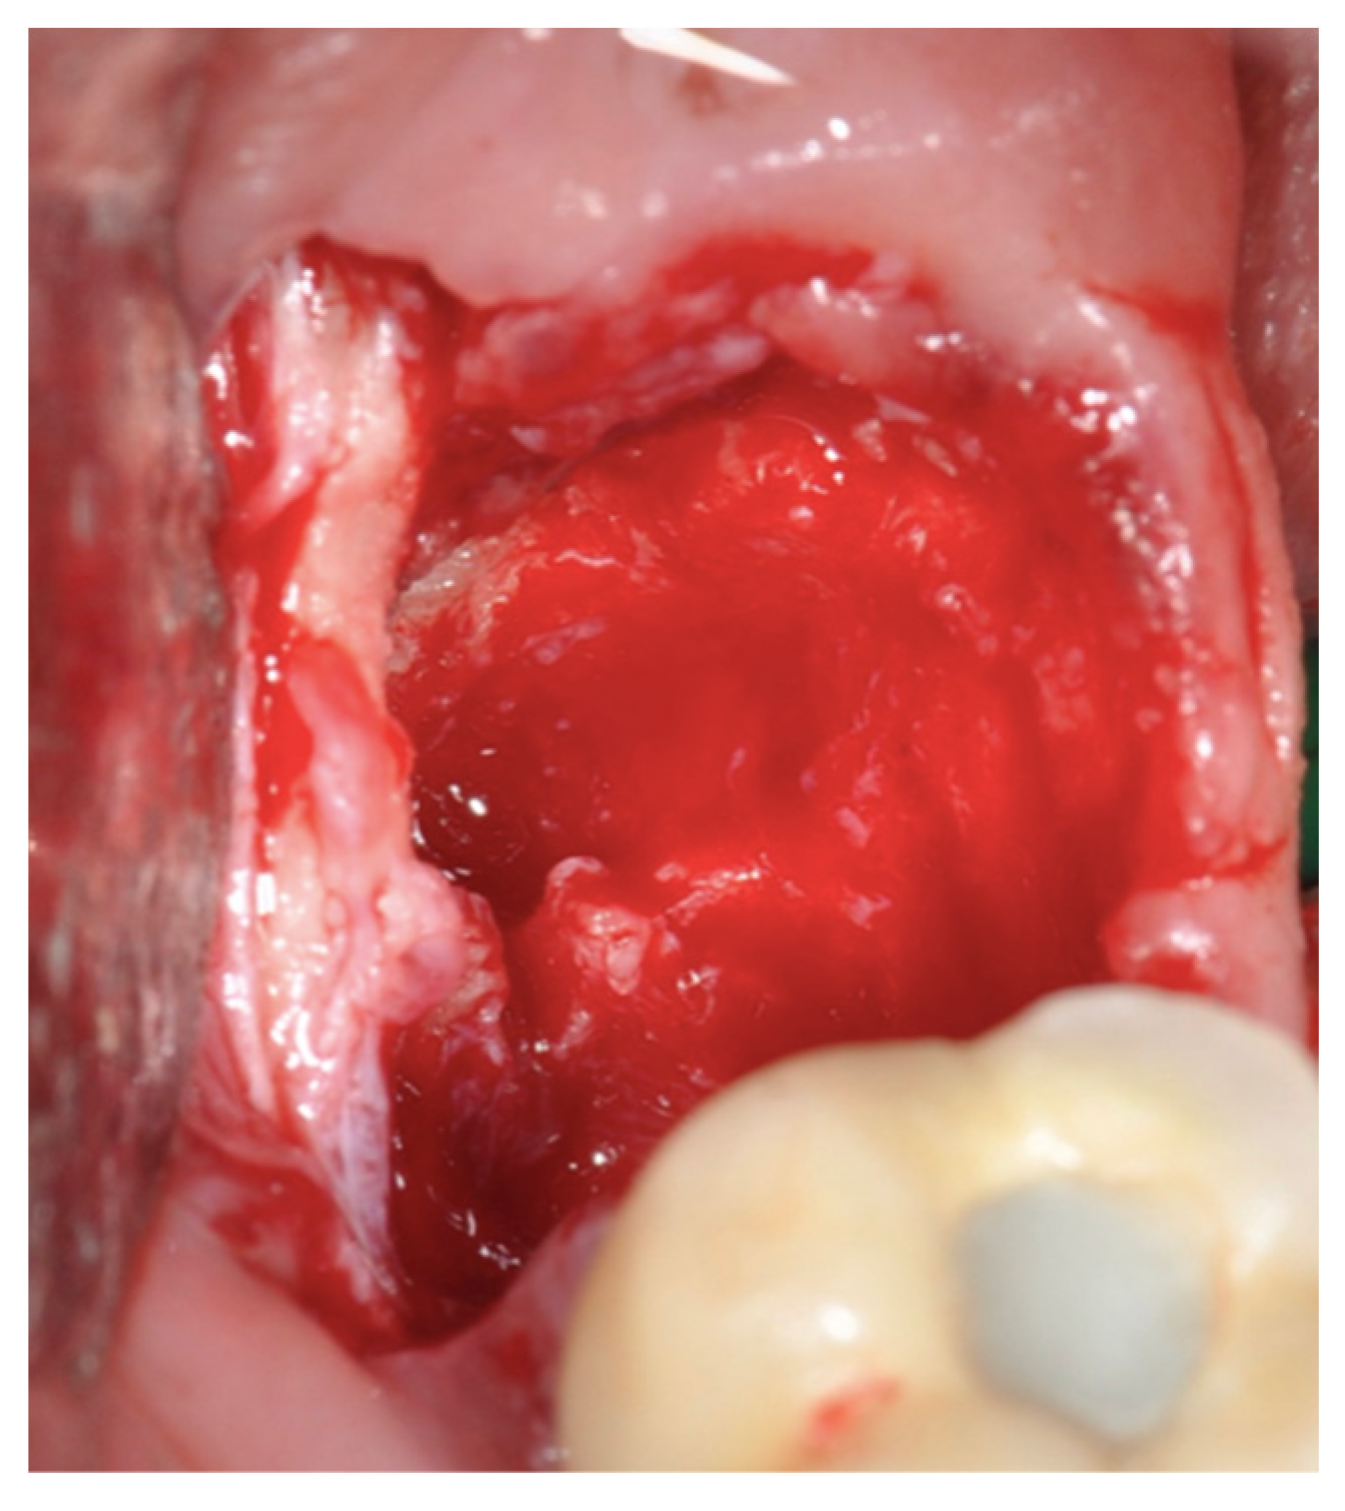

New Operative Protocol for Immediate Post-Extraction Implant in Lower-First-Molar Region with Rex-Blade Implants: A Case Series with 18 Months of Follow-Up

2.2. Surgical Technique